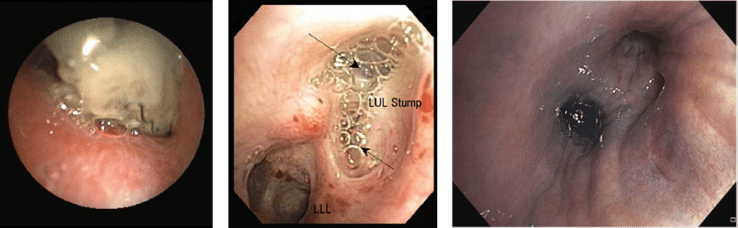

การส่องกล้องตรวจหลอดลมเป็นการตรวจที่สำคัญเนื่องจากช่วยในการวินิจฉัยภาวะแผลรูเชื่อมระหว่างหลอดลมและช่องเยื่อหุ้มปอด โดยเฉพาะในรายที่รอยรั่วอยู่ในหลอดลมแขนงใหญ่ส่วนกลาง หรือในรายที่เข้ารับการผ่าตัดทรวงอกมาก่อน นอกจากนี้ยังเป็นการช่วยตรวจแยกวินิจฉัยโรคอื่นๆที่มีลักษณะอาการใกล้เคียงกันได้ โดยเฉพาะโรคปอดอักเสบติดเชื้อและวัณโรค โดยอาจพบลักษณะแผลที่เป็นรอยรั่วขอบเขตชัด แผลที่เป็นรอยรั่วที่มีเนื้อตาย (necrotic tissue) ปกคลุมอยู่ หรือในบางครั้งที่ลักษณะแผลผ่าตัดอาจพบว่าปกติได้ โดยในรายที่เห็นรอยรั่วดังกล่าวไม่ชัดเจน อาจใช้วิธีการพรมน้ำเกลือผ่านทางกล้องส่องหลอดลม ลงบนพื้นผิวบริเวณดังกล่าว แล้วสังเกตฟองอากาศที่จะเกิดขึ้น นอกจากนี้ยังมีรายงานการใช้สาร methylene blue ฉีดเข้าช่องเยื่อหุ้มปอดผ่านทางสายระบายจากทรวงอก (chest drain) ร่วมกับการส่องกล้องหลอดลม โดยการดูสี methylene blue ที่ซึมผ่านเข้ามาในหลอดลม เพื่อช่วยระบุตำแหน่งของรอยรั่วที่ผู้ป่วยมี ดังรูปที่ 3

แสดงรอยแผลผ่าตัดหลอดลม (bronchial stump) ที่มีเนื้อตายปกคลุมอยู่ กลาง

แสดงฟองอากาศที่เกิดขึ้นบนรอยรั่วบนรอยแผลผ่าตัดหลอดลม ขวา

ภาพหลอดลมที่มีสี methylene blue ซึมผ่านจากช่องเยื่อหุ้มปอดเข้ามาภายในหลอดลม